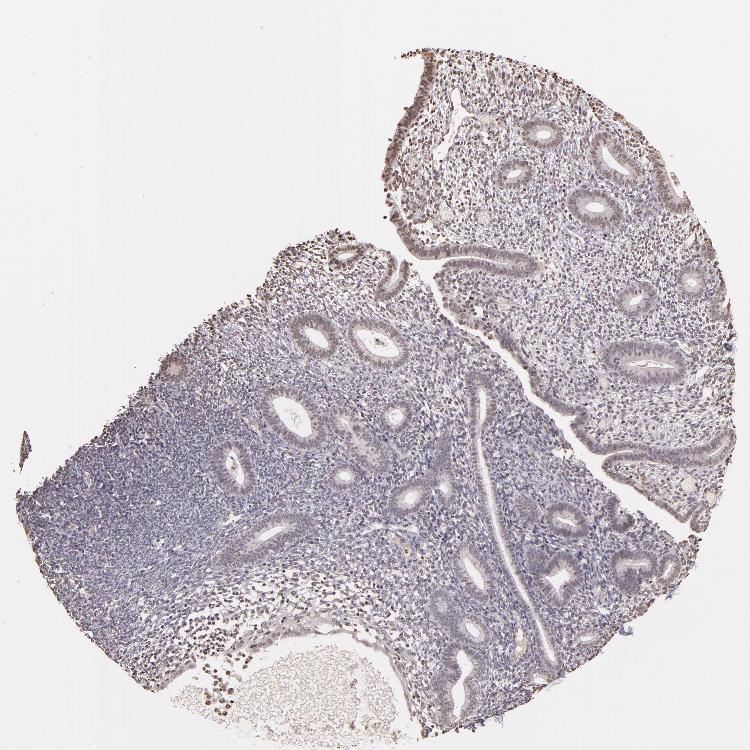

ENDOMETRIUM 2 - Antibody stainingi

Antibody staining in the annotated cell types in the current human tissue is reported as not detected, low, medium, or high, based on conventional immunohistochemistry profiling in selected tissues. This score is based on the combination of the staining intensity and fraction of stained cells.

Each image is clickable and will lead to virtual microscopy that enables deeper exploration of all samples and also displays staining intensity scores, fraction scores and subcellular localization as well as patient and tissue information for each sample.

Antibody CAB002008Antibody CAB002009

Cells in endometrial stroma Not detectedLow

Glandular cells Not detectedLow